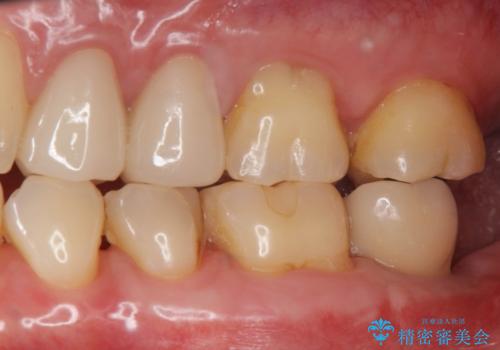

歯からの異臭 虫歯の再発からのインプラント治療

- 「歯から異臭がする。」とのことで相談に来院されました。

X線検査を行ったところ、セラミッククラウン下に虫歯が再発し、歯の破折も認めました。

歯の抜去を行い、骨の造成を含めたインプラントによる咬合機能の回復を図ります。

- 44万円(インプラント・チタンカスタムアバットメント・ジルコニアクラウン・仮歯)費用は治療当時の料金となります

X線を撮ることで、外から見てもわからない、歯の問題点をより正確に把握することができます。